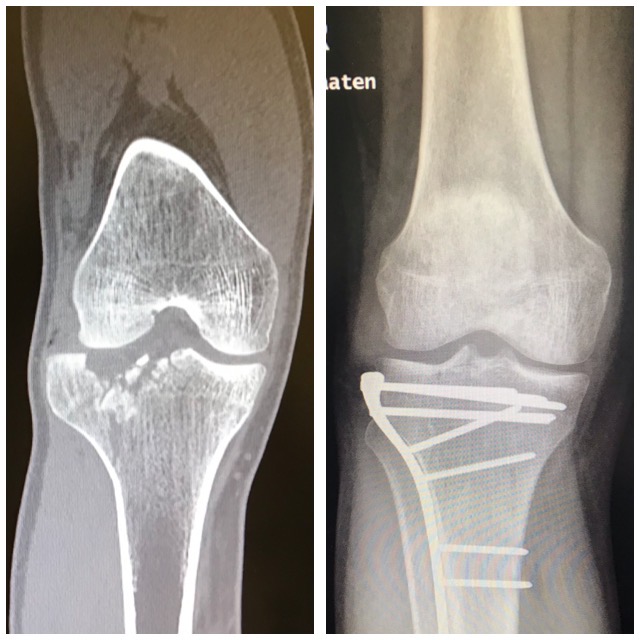

Polven

alueen murtuma

Ennen – Jälkeen